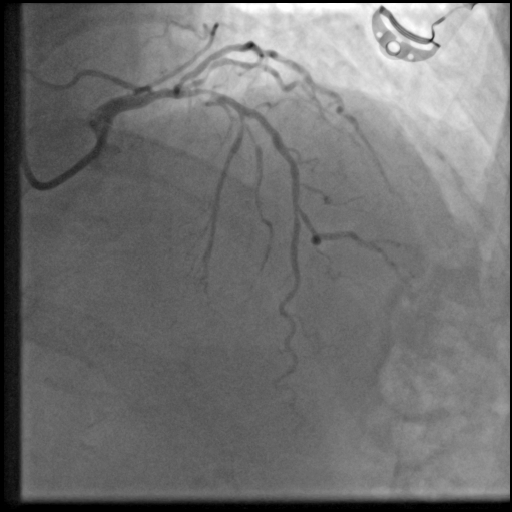

To further assess the detection performance, qualitative results for three test images are presented in Figure 2. The first column shows the original images with ground truth annotations. The second, third, and fourth columns depict detections from DINO-DETR, Grounding DINO, and YOLO, respectively.

(a) Original (b) DINO-DETR (c) Grounding DINO (d) YOLO

The qualitative comparison in Figure 2 reinforces the trends observed in the quantitative evaluation. DINO-DETR produced fewer detections, occasionally missing relevant stenotic regions, consistent with its conservative detection strategy aimed at minimizing false positives [6]. Grounding DINO, although capable of identifying more regions, sometimes resulted in cluttered predictions due to over-detections [7]. YOLO provided a reasonable trade-off by effectively capturing anatomical structures while maintaining relatively high confidence scores and clear visualizations [5].